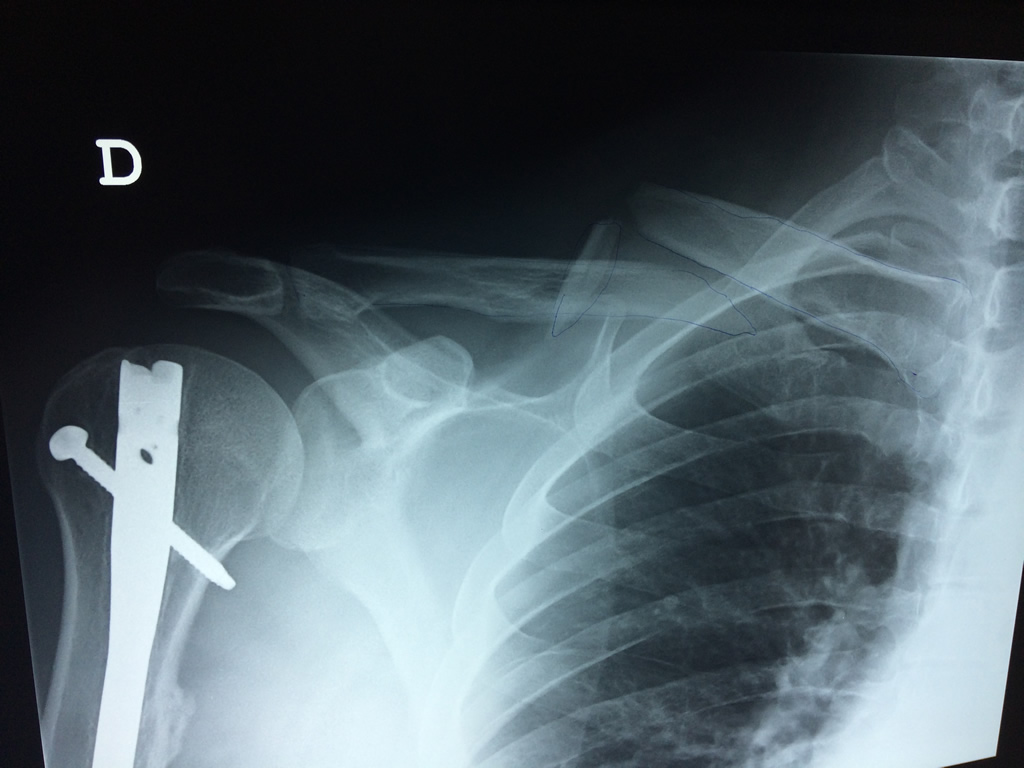

La clavícula es un hueso largo, con forma de "S" itálica, situado en la parte anterosuperior del tórax. Junto con la escápula forman la cintura escapular. Se puede palpar por toda su longitud y se extiende del esternón al acromion de la escápula, siguiendo una dirección oblicua lateral y posterior.